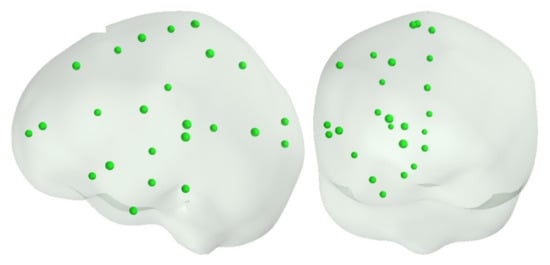

3.2. Source Dipoles at 50 Cortical Locations

3.3. Source Dipoles on Cortical Surfaces